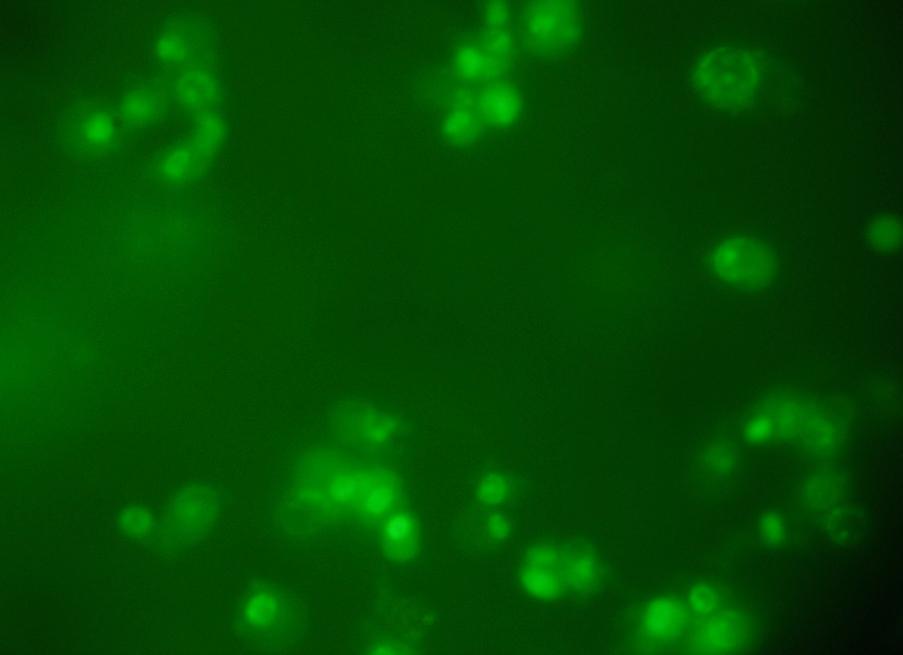

To better understand morphological change of Hep 3B cells after silver nanoparticles treatment, the cells were observed under acridine orange/ethidium bromide (AO/EB) double staining after treatment at different time points of silver nanoparticles. The figure shows. that the Silver Nanoparticles induced apoptosis after 24 and 48 hours incubation. Cells stained green represent viable cells (Figure 4a), whereas bright greenish yellow staining represented early apoptotic cells, and reddish or orange staining represents late apoptotic cells. As shown in (Figure 4b) Hep 3B cells after 24 hours treatment showed slight changes in cellular morphology, including chromatin condensation and fragmented nuclei. On the other hand, (Figure 4c) show higher number cells with increased chromatin condensation with increased fragmented nuclei thus it represents increase in the number of apoptotic cells after 48 hours of treatment.

Fig. 4c: 48 hrs after treatment of Hep 3B cell line with IC50 concentration

Therefore, using the AO/EB staining procedure, the morphological features of a Hep 3Bcell line in apoptosis were time dependent, i. e., a stronger apoptosis signal was induced with increase in the time. The cytotoxic effects of SNPs, probably due to the fact that SNPs may interfere with the proper functioning of cellular proteins and induce subsequent changes in cellular chemistry [17.18] reported a significant cytotoxicity of AgNPs in BRL 3A rat liver cells.